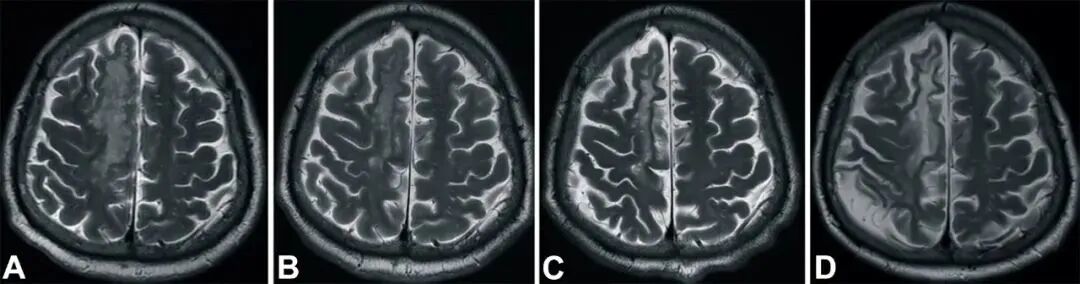

梗死发生后 2 小时、8 天、3 个月和 6 个月获得的 T2 加权图像显示右侧放射冠的白色强度增加(A到D)